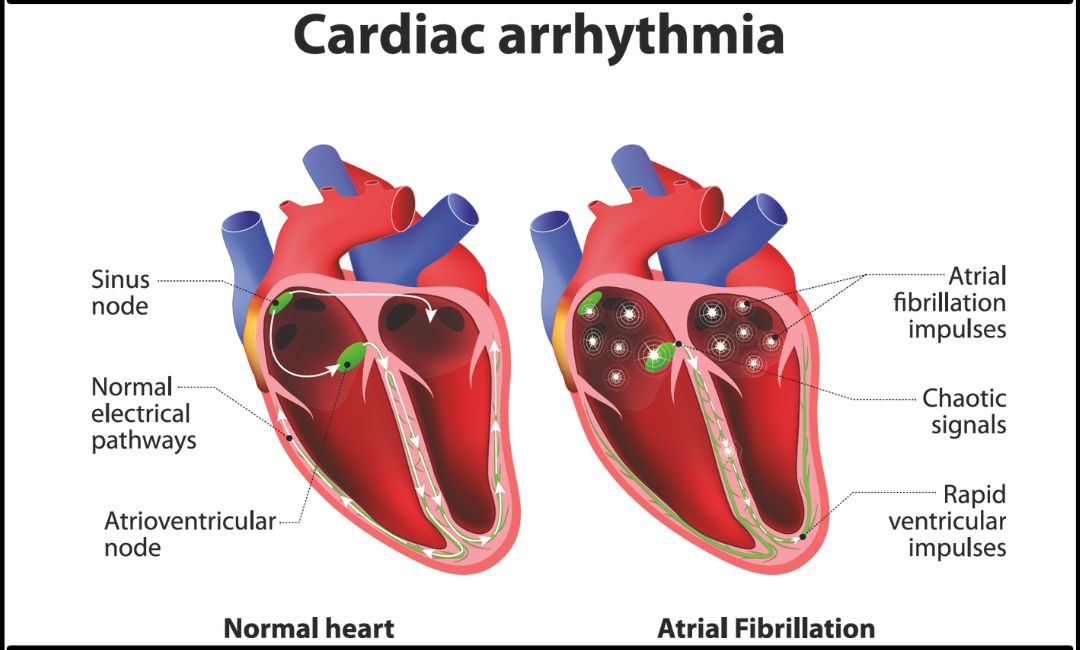

Heart Arrhythmia: Causes, Risk Factors, Symptoms, Treatment

continentalhospitals.comHeart arrhythmia: Causes, Risk Factors, Symptoms, Treatment

continentalhospitals.comHeart arrhythmia: Causes, Risk Factors, Symptoms, Treatment

What Are Arrhythmias And Why Are They Dangerous?: Cardiovascular

www.cardiologytampa.comWhat Are Arrhythmias and Why are they Dangerous?: Cardiovascular …

www.cardiologytampa.comWhat Are Arrhythmias and Why are they Dangerous?: Cardiovascular …